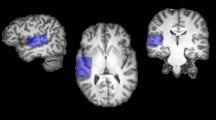

Many nonglutamatergic synaptic terminals in the mammalian brain contain the vesicular glutamate transporter 3 (VGLUT3), indicating that they co-release the excitatory neurotransmitter glutamate. However, the functional role of glutamate co-transmission at these synapses is poorly understood. In the auditory system, VGLUT3 expression and glutamate co-transmission are prominent in a developing GABA/glycinergic sound-localization pathway. We found that mice with a genetic deletion of Vglut3 (also known as Slc17a8) had disrupted glutamate co-transmission and severe impairment in the refinement of this inhibitory pathway. Specifically, loss of glutamate co-transmission disrupted synaptic silencing and the strengthening of GABA/glycinergic connections that normally occur with maturation. Functional mapping studies further revealed that these deficits markedly degraded the precision of tonotopy in this inhibitory auditory pathway. These results indicate that glutamate co-transmission is crucial for the synaptic reorganization and topographic specification of a developing inhibitory circuit.